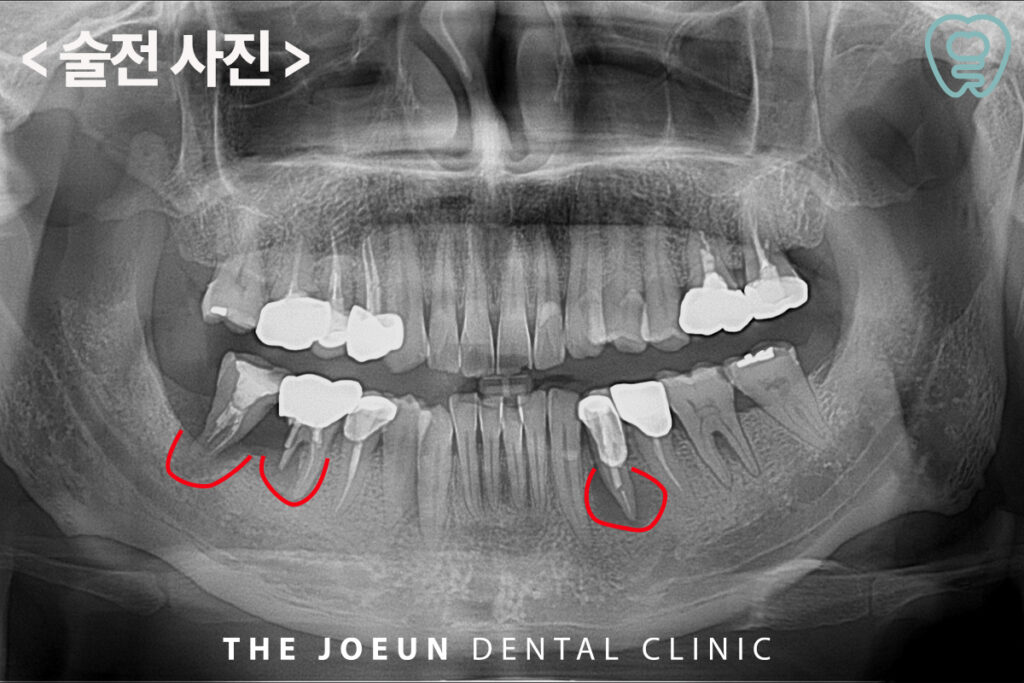

오늘은 심한 골 파괴로 인해 발치 후 뼈 이식을 선행한 뒤, 임플란트를 식립하여 완성하신 환자분을 소개해 드리도록 하겠습니다. 환자분께서는 아래쪽 치아 잇몸이 피곤하거나 컨디션이 좋지 않을 때 붓기도 하고 양치할 때 피도 나오신다며 내원해 주셨습니다.

파노라마 사진을 촬영해 보았을 때 확연하게 양쪽 아래 큰 어금니와 작은 어금니 부위 크라운으로 수복되어 있는 치아들의 뿌리에 커다란 염증으로 인해 이미 잇몸뼈를 많이 녹인 상태임을 확인할 수 있었습니다. 이미 많은 시간이 지나 남아 있는 치조골 유지를 위해 발치 후 치조골 이식을 진행하여 임플란트 식립을 위한 상태를 만들어준 후 임플란트를 진행하는 것으로 계획을 수립하였습니다.